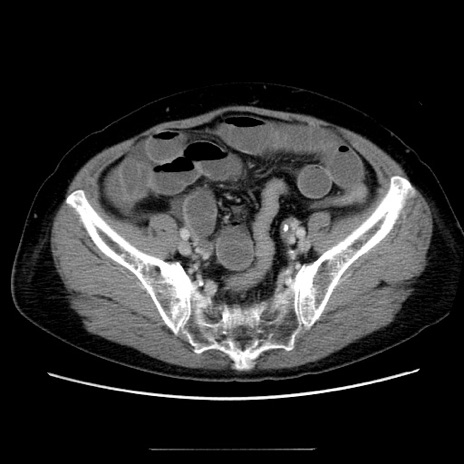

症例5(横断像)

【症例】70歳代女性

【主訴】お腹が張る

【現病歴】1週間くらい前から腹部膨満の自覚あり。昨日夜から増悪したため、本日救急外来受診。

【身体所見】意識清明、BT 36.5℃、BP 165/106mmHg、HR 80bpm、SpO2 98%、腹部:膨満、軟、自発痛・圧痛なし、触診にて不快感あり、腸蠕動音:減弱

【データ】WBC 12600、CRP 1.04